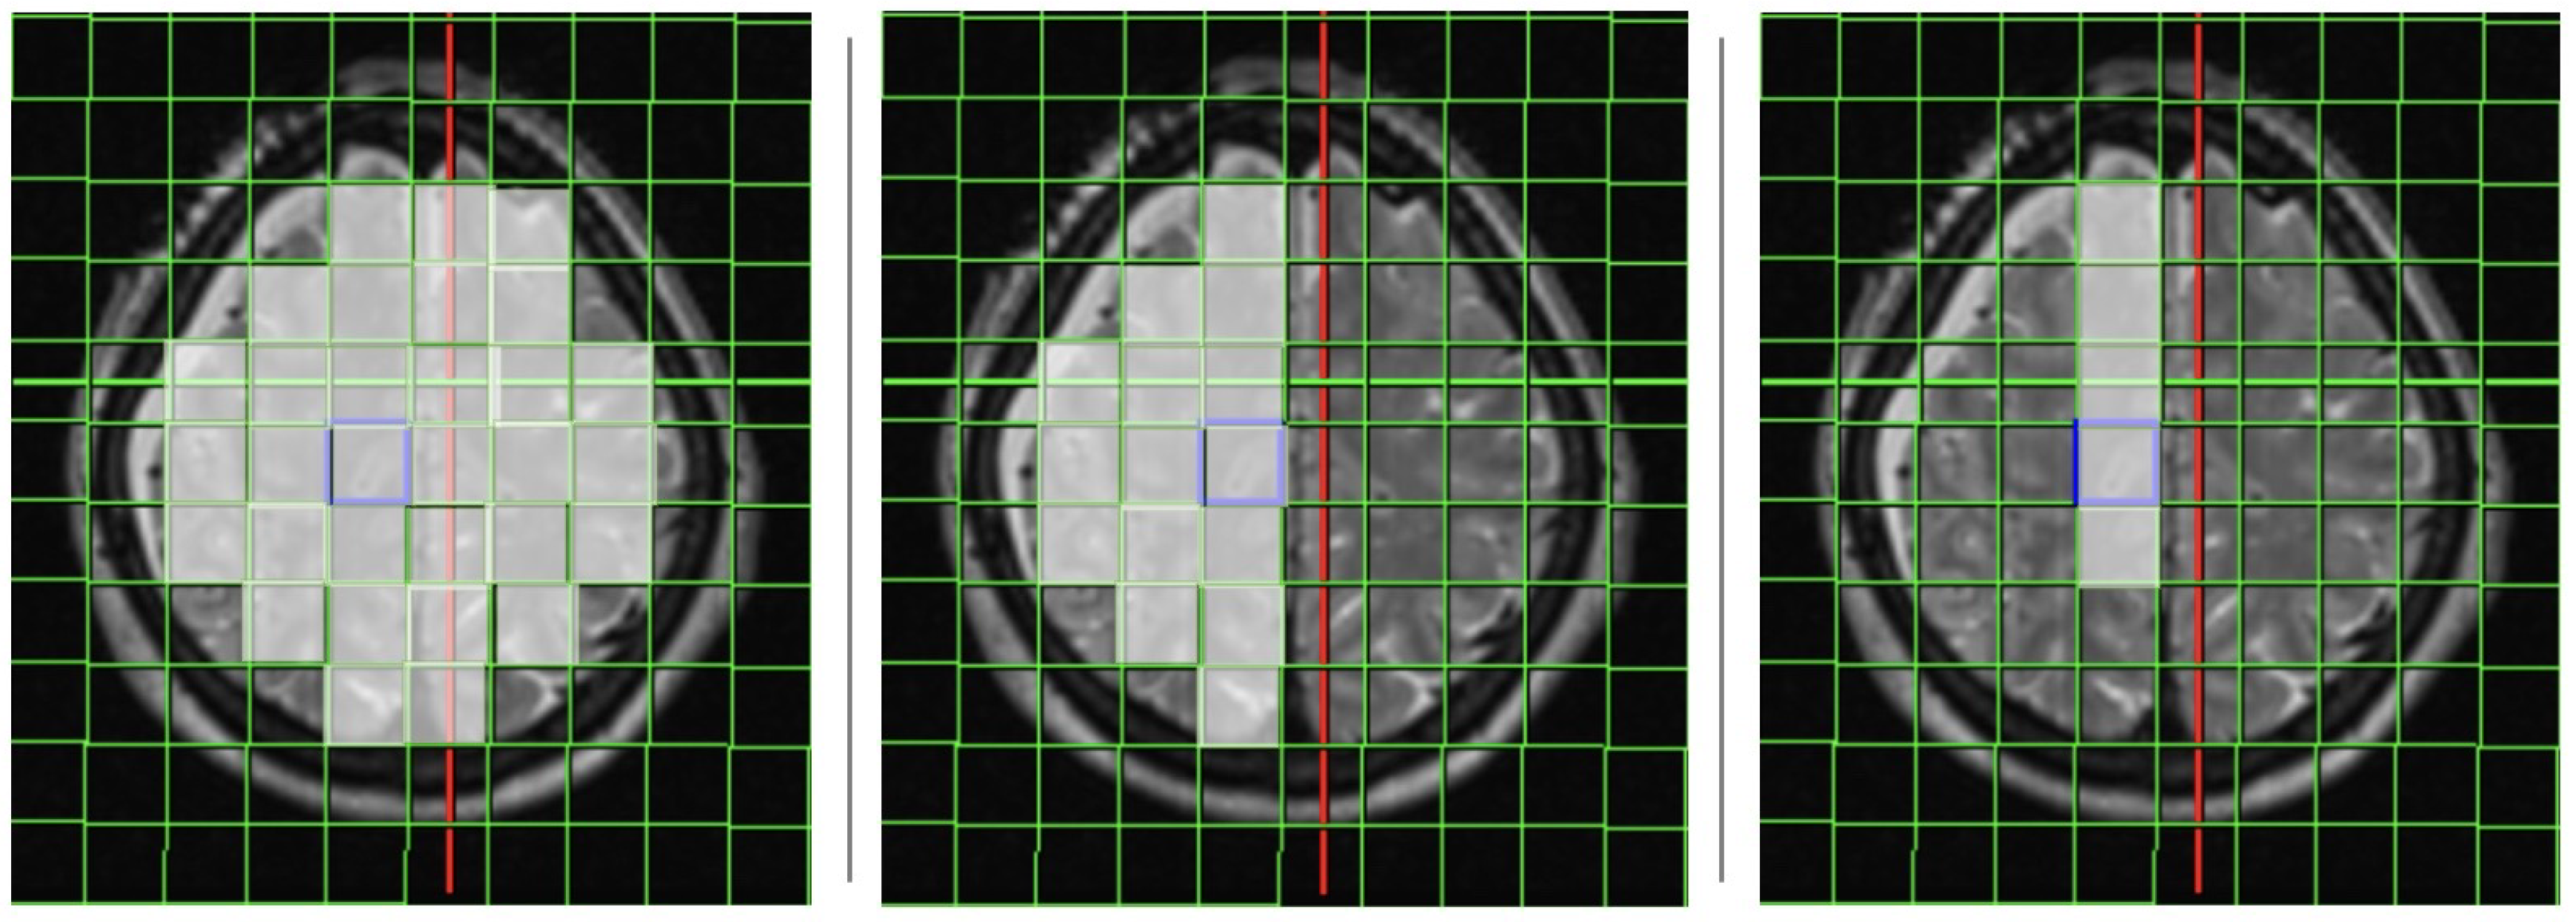

The analysis of the 31P-MRS data took place in all investigated voxels (cumulative results), and separately only in the affected side, and in the arterial territory of the affected artery. The positioning of the voxels is shown in Figure 1.

Figure 1. Positioning of the 31P-MRS voxels in a patient with ruptured ACA-Aneurysm right: all voxels (left), only affected side (middle) and only affected territory (right)